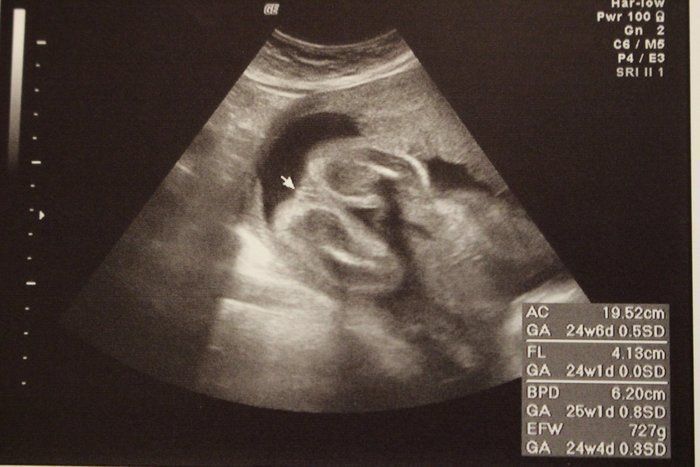

チャーミー小結さんの妊娠24週目のエコー写真

2D画像。医師から「今、性別を知りたいですか?それとも楽しみに取っておきますか?」と尋ねられ、名付けや準備に必要だからと教えてもらいました。前夜にみた夢のお告げ通りだったので、ますます神秘的な気持ちになりました。